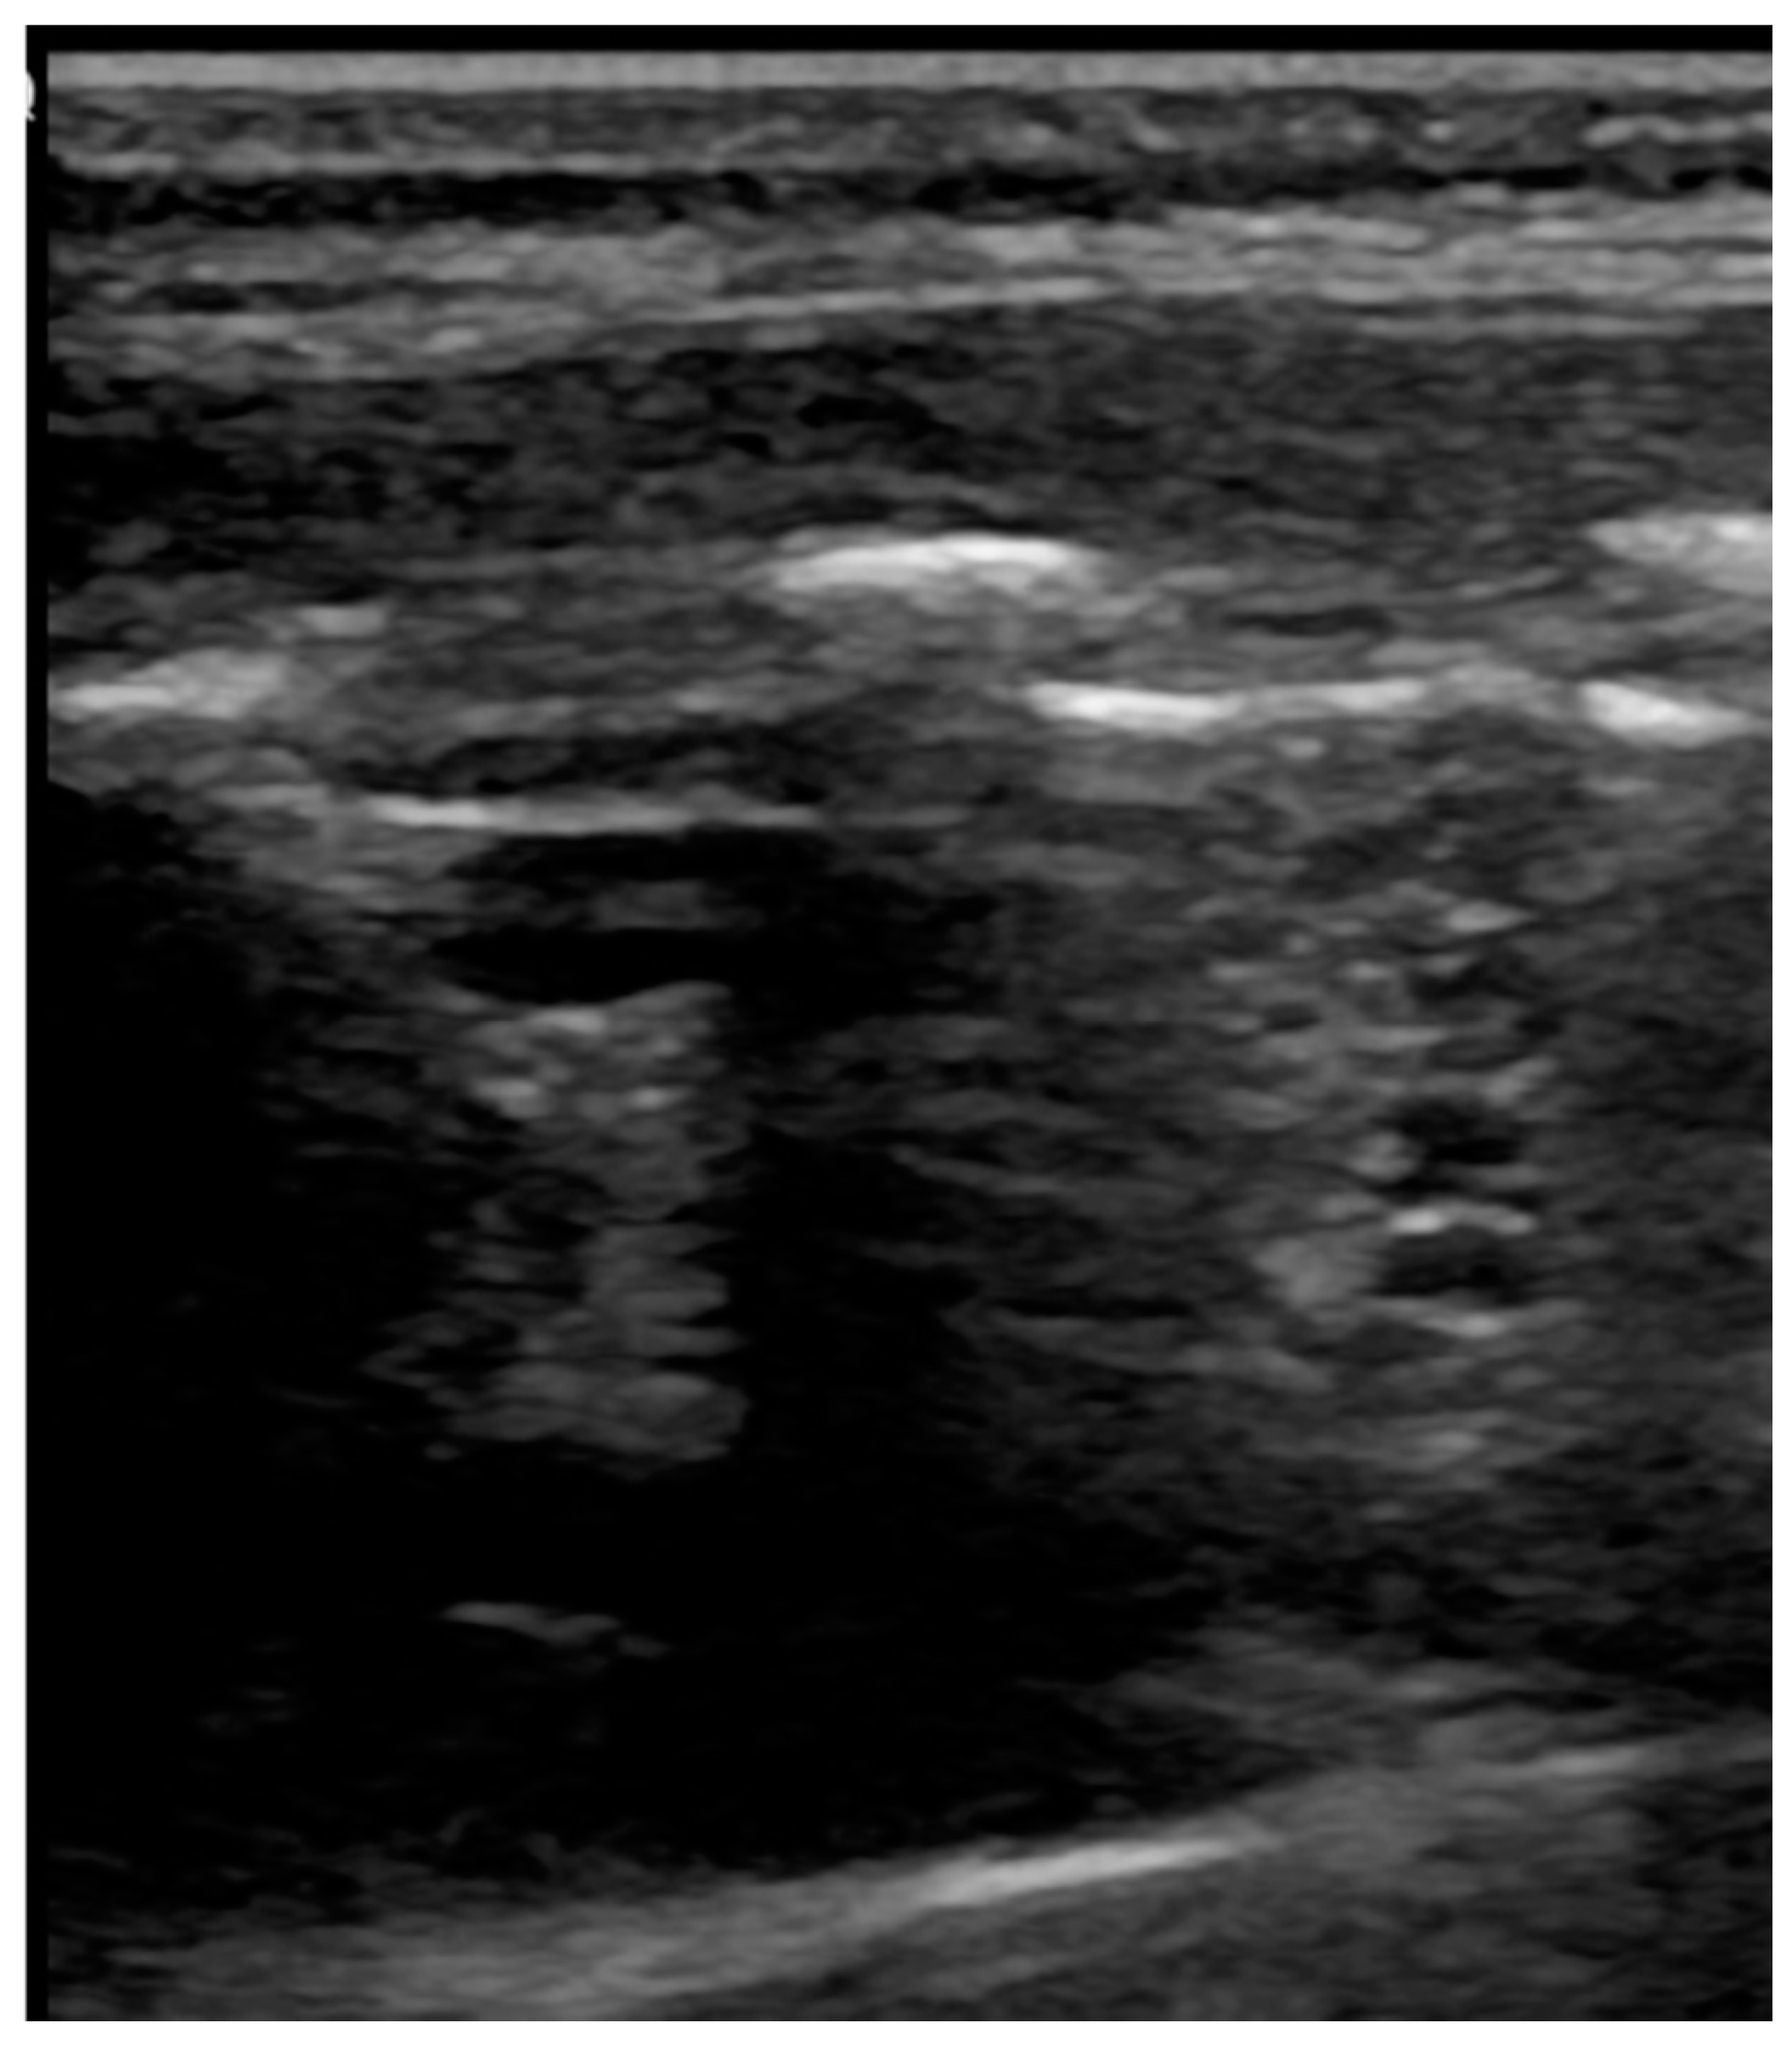

4.3. Pneumonia

4.4. Atelectasis